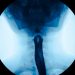

Most colon polyps don’t cause any symptoms, but some people experience rectal bleeding or blood in their stool, abdominal pain or constipation. If you have these symptoms, your doctor may order a test called a barium enema or a colonoscopy to find out if you have polyps.

If you have polyps, your doctor can remove them during a test called a colonoscopy. A colonoscopy uses a long, thin tube with a light and camera at the end to examine your colon for polyps. Your doctor will tell you what to expect during the procedure.